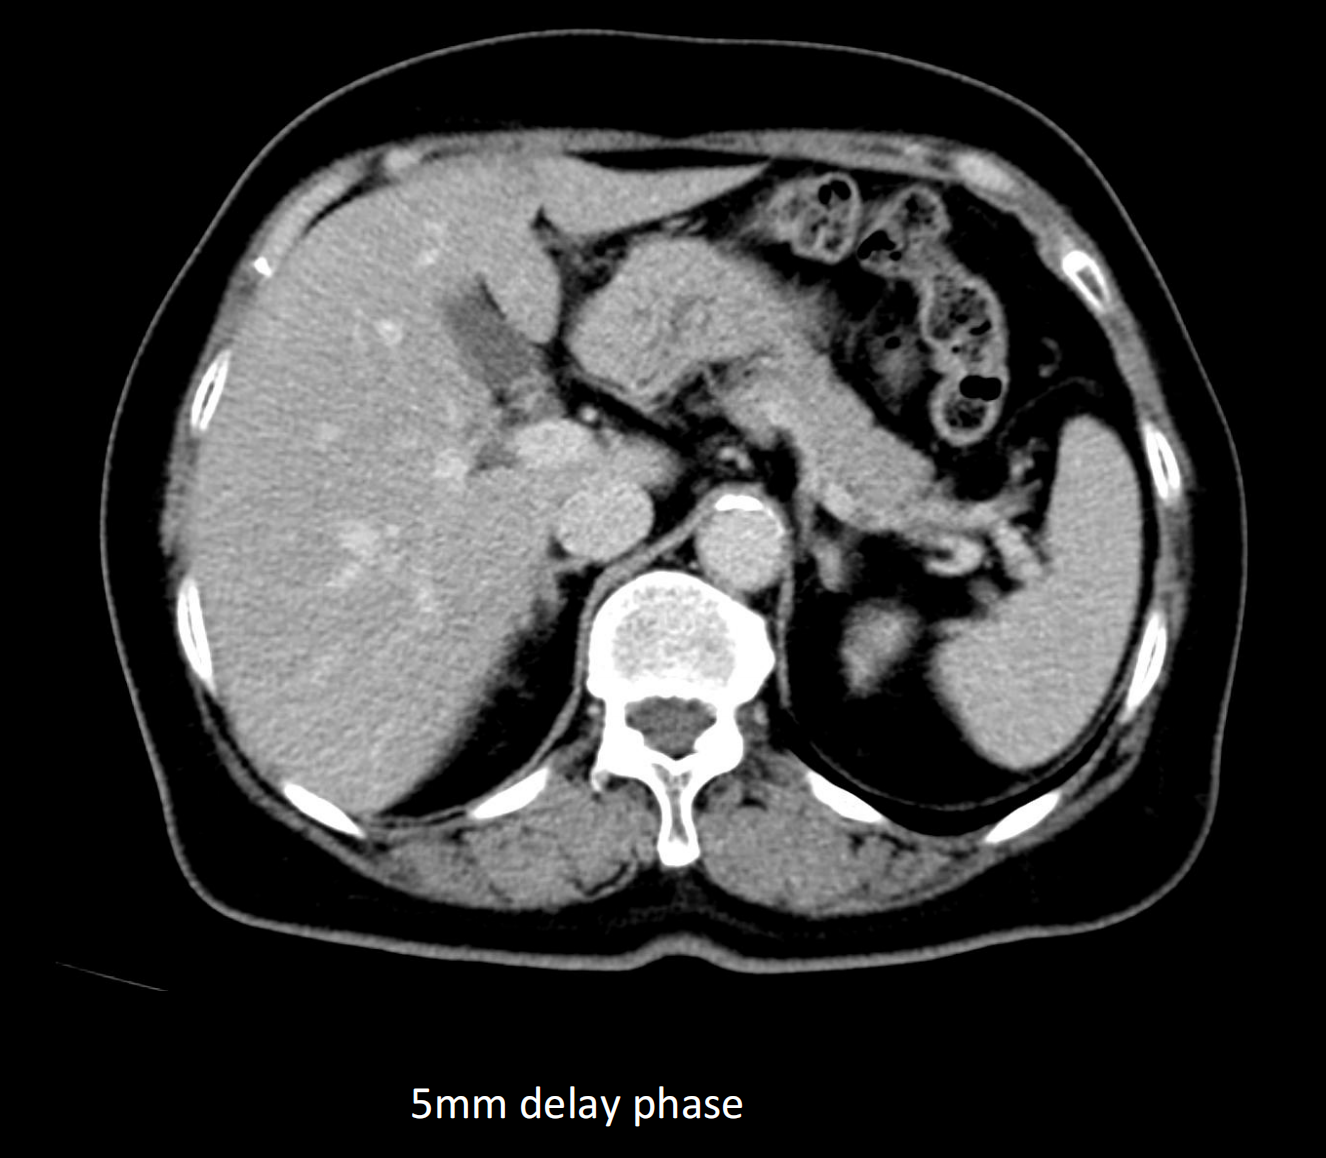

- Giải pháp chẩn đoán hình ảnh mô mềm tiên tiến cho khảo sát ổ bụng

- Tối ưu chất lượng hình ảnh chẩn đoán và giảm phơi nhiễm bức xạ

- Đảm bảo chất lượng hình ảnh chẩn đoán cao